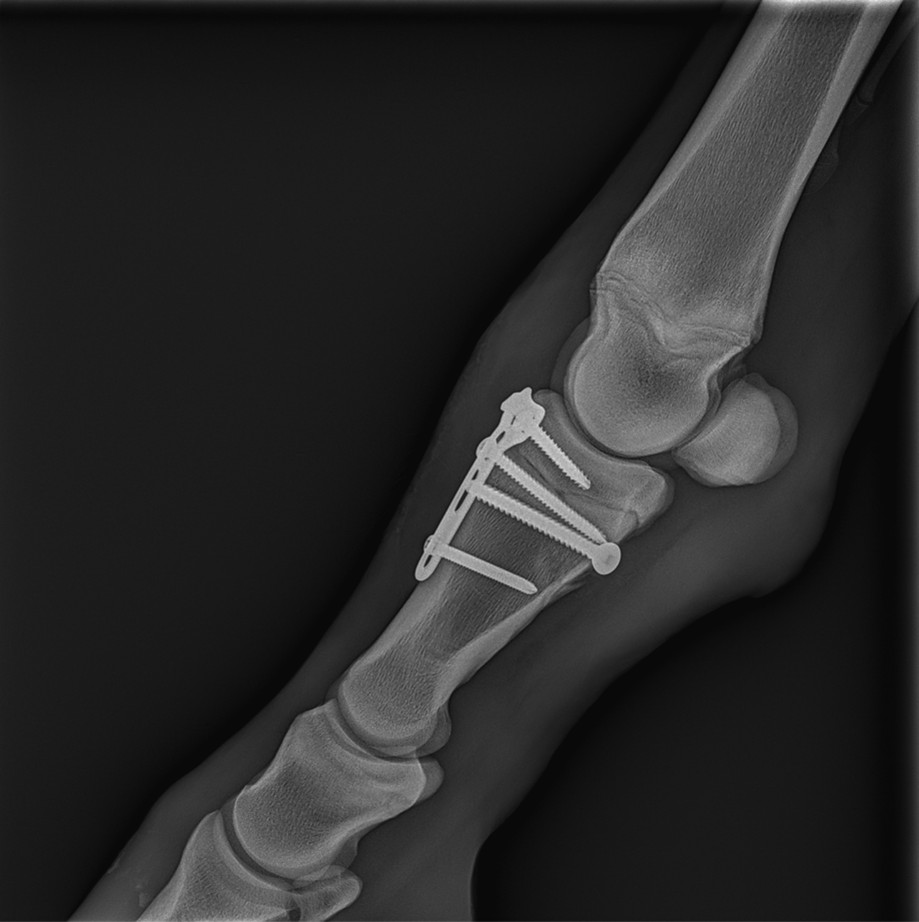

The following day, the fracture was surgically repaired under general anesthesia using a combination of cortical screws and a plate. With fracture reduction achieved under intraoperative radiographic guidance, stabilization was completed without complications. The foal was comfortable in the immediate postoperative period.

Figure 4: Post-operative lateromedial radiograph of the left hind limb.